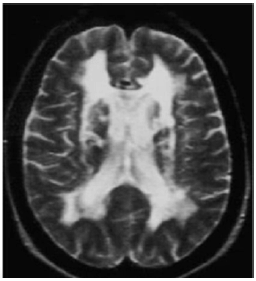

Paciente de 57 anos apresenta quadro de dificuldade motora com lentidão e marcha com pequenos passos e instabilidade postural. Roda denteada ausente. Apresenta dificuldade de encontrar palavras (afasia de expressão) e períodos de confusão mental. Ao longo de 2 anos, foi apresentando declínio cognitivo perceptível e evoluiu com incontinência urinária. A RM apresenta leucoencefalopatia periventricular, acompanhada por múltiplos infartos na substância branca (imagem abaixo). O declínio cognitivo impactou sua funcionalidade tornando-a dependente para atividades instrumentais de vida diária.

A descrição clínica e o exame de imagem sugerem o diagnóstico de Demência